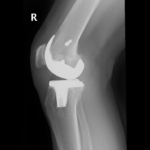

The surgery is performed under spinal or general anesthesia. Your surgeon will make an incision in the skin over the affected knee to expose the knee joint. Then the damaged portions of the femur bone are cut at appropriate angles using specialized jigs. The femoral component is attached to the end of the femur with or without bone cement. The surgeon then cuts or shaves the damaged area of the tibia (shinbone) and the cartilage. This removes the deformed part of the bone and any bony growths, as well as creates a smooth surface on which the implants can be attached. Next, the tibial component is secured to the end of the bone with bone cement or screws. Your surgeon will place a plastic piece called an articular surface between the implants to provide a smooth gliding surface for movement. This plastic insert will support the body’s weight and allow the femur to move over the tibia, similar to the original meniscus cartilage. The femur and the tibia with the new components are then put together to form the new knee joint. To make sure the patella (knee cap) glides smoothly over the new artificial knee, its rear surface is also prepared to receive a plastic component. With all the new components in place, the knee joint is tested through its range of motion. The entire joint is then irrigated and cleaned with a sterile solution. The incision is carefully closed, drains are inserted and a sterile dressing is placed over the incision.